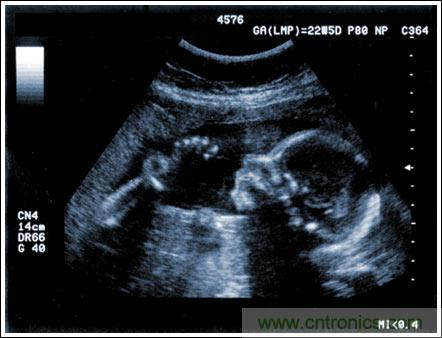

通過發(fā)射超聲能量進入人體,接收并處理返回的反射信號,相控陣超聲系統(tǒng)可以生成體內(nèi)器官和結構的圖像,映射血液流動和組織運動,同時提供高準確度的血流速度信息。傳統(tǒng)設計中,構建這樣的成像系統(tǒng)需要大量的高性能相控陣發(fā)射器和接收器,使得車載設備體積龐大且價格昂貴。近年來,隨著集成工藝的進步,設計人員能夠獲得小尺寸、低成本而且高度便攜的成像系統(tǒng)方案,并可達到接近大型成像設備的性能指標。而新的設計挑戰(zhàn)依然存在,即在進一步提高方案集成度的同時提高系統(tǒng)性能和診斷能力。